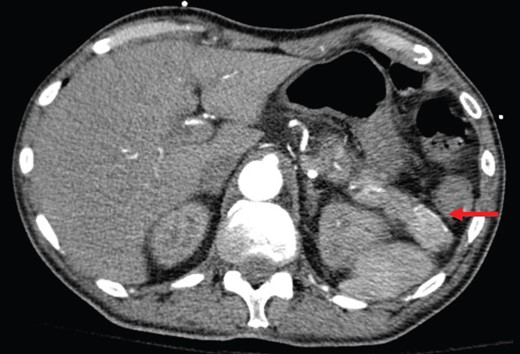

Abdominal CT shows a 2.2-cm arterial enhancing lesion (marked by red arrow) in tail of pancreas consistent with an insulinoma.

Based on sustained hypoglycemia, inappropriate insulin and C-peptide secretion on repeated measures, and the presence of the arterially enhancing mass in the pancreatic tail, a decision was made to proceed with distal pancreatectomy and splenectomy. Intraoperatively, a mass corresponding with preoperative imaging was appreciated. Laparotomy revealed no evidence of other intraabdominal macroscopic disease. Intraoperative ultrasound was considered but not readily available as surgery was carried out in emergency evening hours.